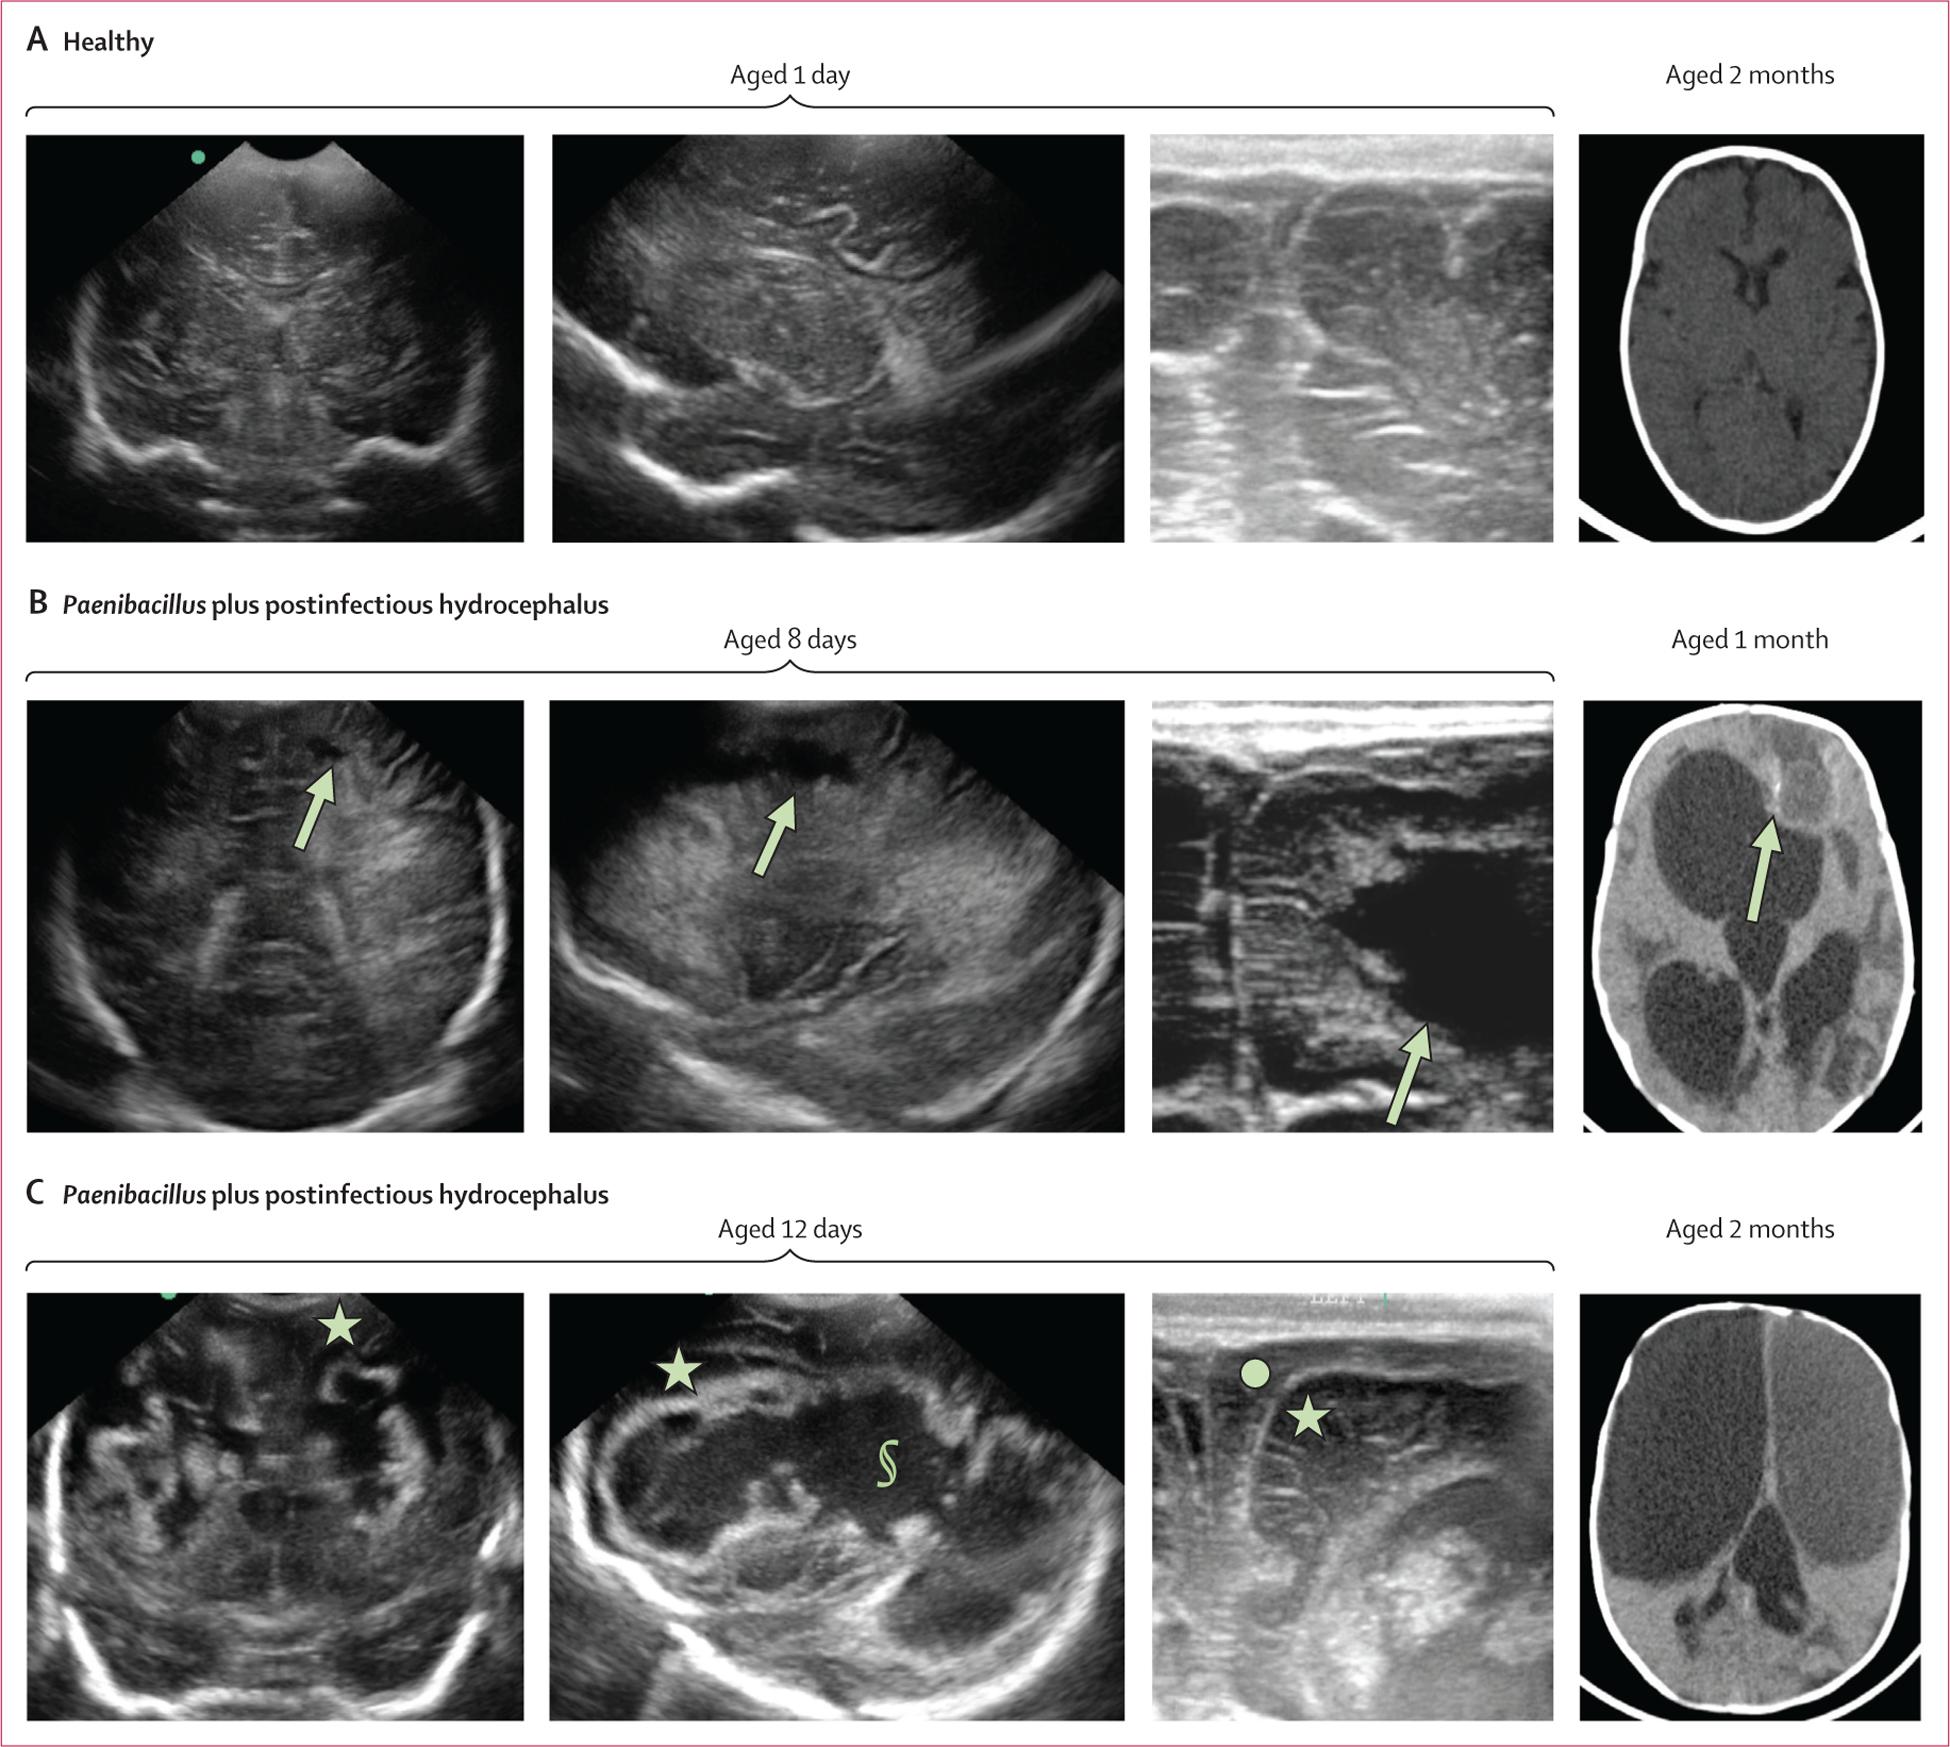

No Paenibacillus spp were detected in vaginal, maternal blood, placental, or cord blood specimens from the mother-newborn cohort by qPCR. Paenibacillus spp was detected in 6% (37 of 631 neonates) in the sepsis cohort and, of these, 14% (5 of 37 neonates) developed postinfectious hydrocephalus. Paenibacillus was the most enriched bacterial genera in postinfectious hydrocephalus CSF (91 [44%] of 209 patients) from the hydrocephalus cohort, with 16S showing 94% accuracy when validated by qPCR. Imaging showed progression from Paenibacillus spp-related meningitis to postinfectious hydrocephalus over 1-3 months. Patients with postinfectious hydrocephalus with Paenibacillus spp infections were geographically clustered.

qPCR 未在母亲-新生儿队列的阴道、母亲血液、胎盘或脐带血标本中检测到蜡状芽孢杆菌属。在败血症队列中,6%(631 名新生儿中的 37 名)检测到蜡状芽孢杆菌属,其中 14%(37 名新生儿中的 5 名)发生感染后脑积水。蜡状芽孢杆菌是脑积水队列中感染后脑积水 CSF 中最丰富的细菌属(209 名患者中有 91 名[44%]),16S 通过 qPCR 验证的准确率为 94%。影像学显示蜡状芽孢杆菌相关脑膜炎进展为感染后脑积水,时间为 1-3 个月。患有感染后脑积水和蜡状芽孢杆菌属感染的患者在地理上呈聚集性。